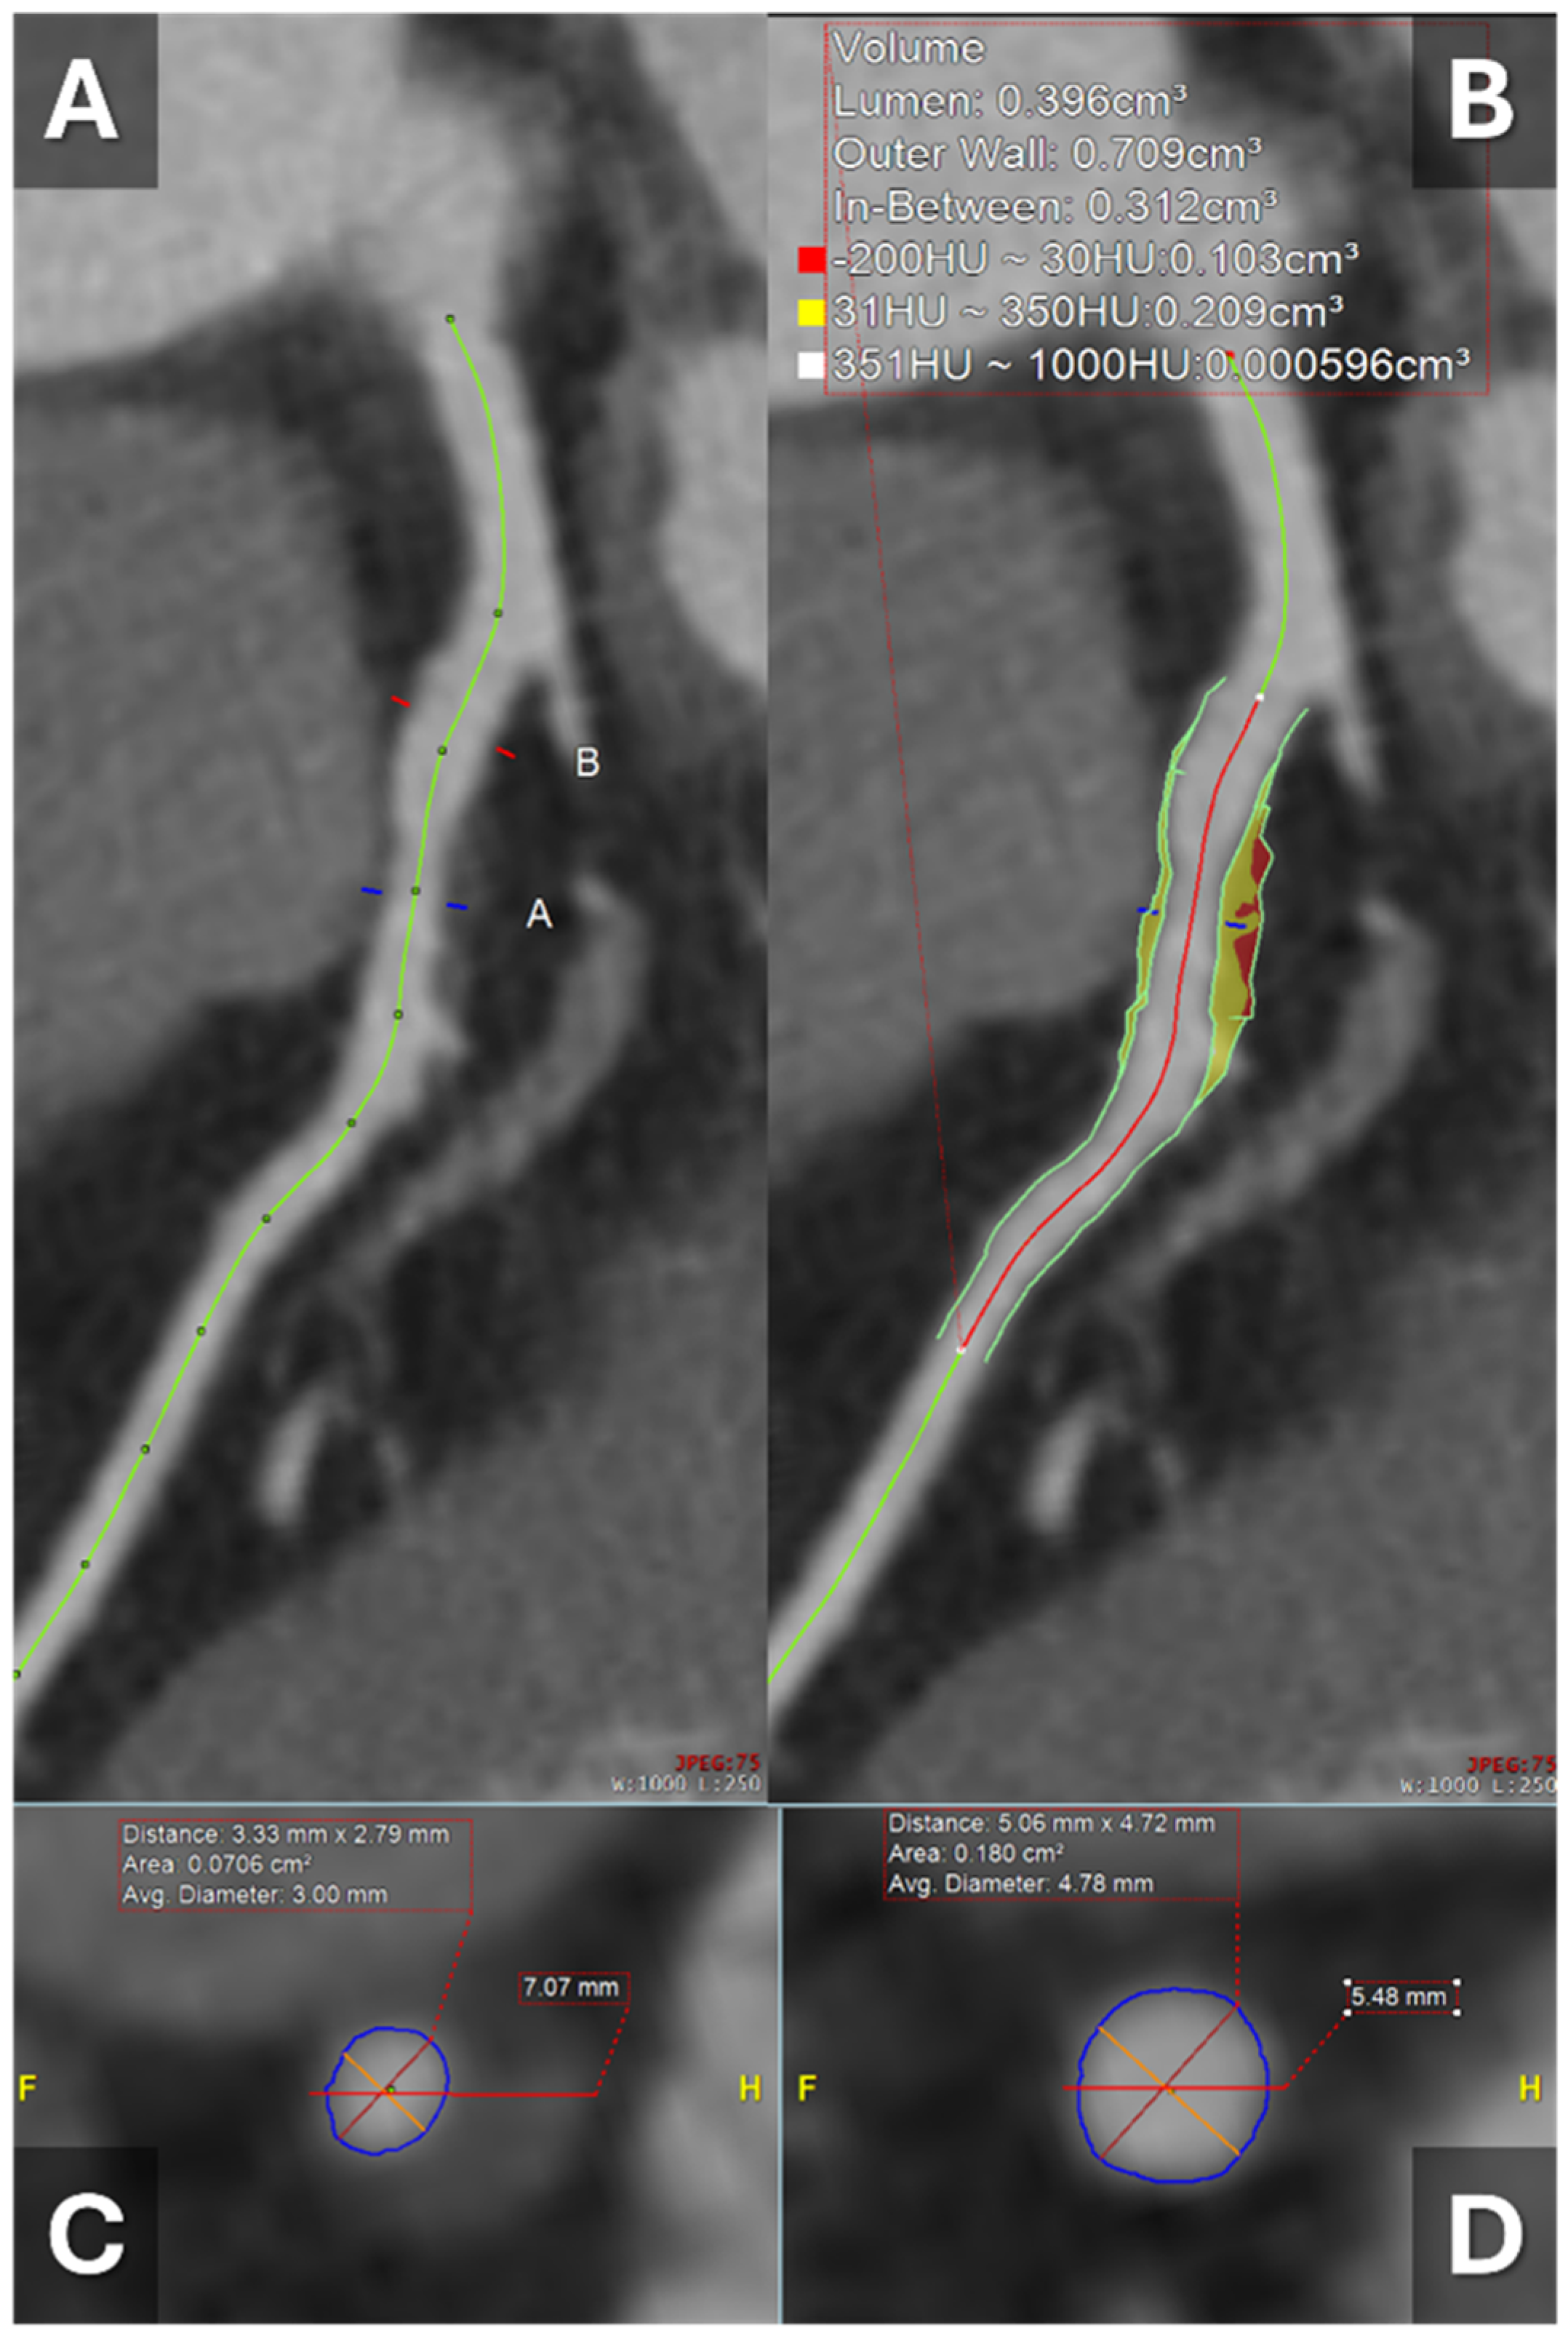

- Yuenyongsinchai, K.; Tan, C.O.; Vranic, J.; Flores, E.; Silverman, S.; Gupta, R. Carotid Plaque Characterization Using Dual-Energy Computed Tomography: Predicting Imminent Ipsilateral Ischemic Stroke in 30 Days. Stroke: Vasc. Interv. Neurol. 2022, 2, e000313. [Google Scholar] [CrossRef]

- Sheta, H.M.; Precht, H.; Busk, C.A.G.R.; Heinsen, L.J.; Nieman, K.; Egstrup, K.; Lambrechtsen, J. Dual-energy CT plaque characteristics of post mortem thin-cap fibroatheroma in comparison to infarct-related culprit lesions. Heart Vessel. 2022, 37, 400–410. [Google Scholar] [CrossRef]